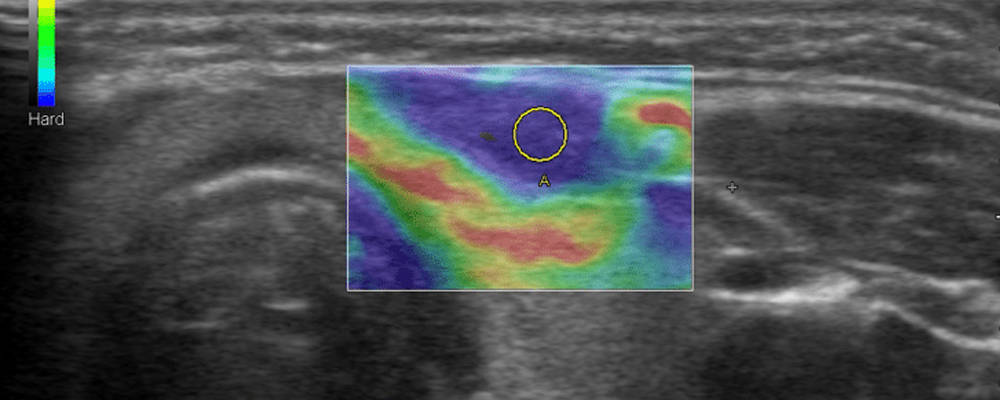

Breast elastography is a new sonographic imaging technique which provides information on breast lesions in addition to conventional ultrasonography (US) and mammography. Elastography provides a noninvasive evaluation of the stiffness of a lesion. Today, two technical solutions are available for clinical use: strain elastography and shear wave elastography. Initial evaluations of these techniques in clinical trials suggest that they may substantially improve the possibility of differentiating benign from malignant breast lesions thereby limiting recourse to biopsy and considerably reducing the number of benign breast biopsy diagnoses. This article reviews the basics of this technique, how to perform the examination, image interpretation and the results of major clinical studies. Although elastography is easy to perform, training and technical knowledge are required in order to obtain images permitting a correct interpretation. This paper will highlight the technique and point out common pitfalls.